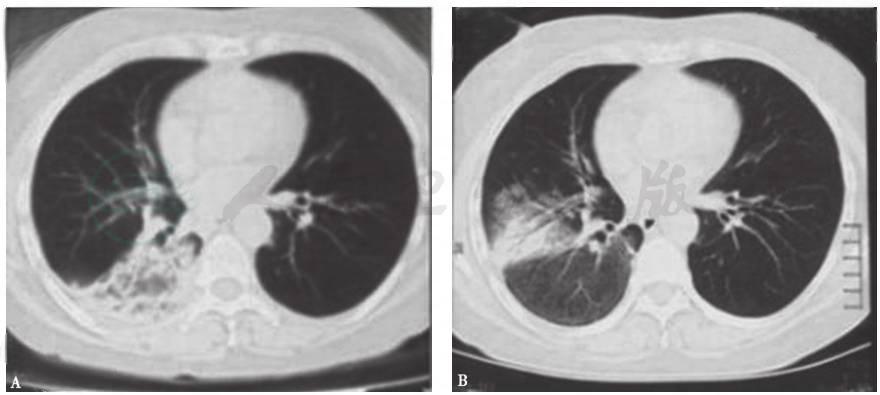

发病第4天,患者于当地医院就诊,胸部CT提示双肺多发结节样改变(图1)。发病第32天,患者转至当地上级医院就诊,胸部CT提示病变较前加重,可见双肺多发大小不一的结节影,部分呈反晕环状,边缘尚清(图2)。

图2发病第32天胸部CT表现

胸部CT:两肺见散在多个片状、花环状高密度影,反晕征,部分密度不均,边缘尚清,部分相互融合,大部分可见含气支气管征(图7)。

患者入院后所做系列检查显示:①肿瘤标志物及大便检查均阴性,结合临床表现,基本上可排除胃肠道肿瘤肺转移;②虽然抗核抗体为1∶100,但其余自身抗体均阴性,结合临床表现,暂不考虑风湿免疫病;③胸部CT提示病变进一步加重;④常规病原学检查均阴性。因此,不排除曲霉菌感染的可能。但患者应用伊曲康唑治疗10天后,复查胸部CT(图8)提示病情进一步加重,且静息状态下动脉血气呈现低氧血症(FiO2 33%,PaO2 64mmHg)。由此推测,本病例可能是由一些非感染非肿瘤性疾病引起。

胸部CT显示,与发病第50天时(图7)相比,双肺原有病灶进一步加重,并出现右侧少量胸腔积液